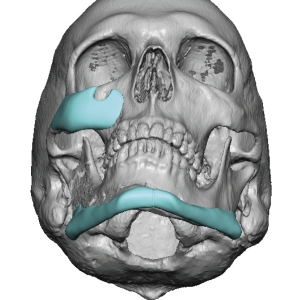

Custom designed or 3D jaw implants are the contemporary workhorse in lower facial asymmetry corrections. With modern patient-specific CT-based implant designing virtual planning an be done to design different right and left dimensions, matching the right and left sides of the jawline and centering the chain can be done far more accurately than stock implants ever could. 3D imaging is important because facial asymmetry is a true 3D problem and standard 2D assessment, even with plain x-rays and 2D CT scans, can not fully appreciate the extent of the asymmetries down to the millimeter level.

Determine the exact bony nature of the asymmetry.

- digitally remove any existing implant materials

- Identify the bony asymmetries

- Facial asymmetry is a multi-dimensional hard and softC tissue problem whose contemporary treatment requires 3D assessment and treatment planning.

- Secondary facial asymmetry surgery will run into prior implant placements and osteotomy fixation hardware which must be considered in the treatment planning.

- Most jaw asymmetries are best treated by a wrap around jawline implant approach to manage the bilateral deformities.

- Cheek flatness/hypoplasia is almost always part of a significant jaw asymmetry.